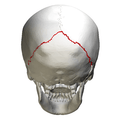

Animation. Lambdoid suture shown in red.

Skull seen from behind. Showing λ-like shape of the lambdoid suture.